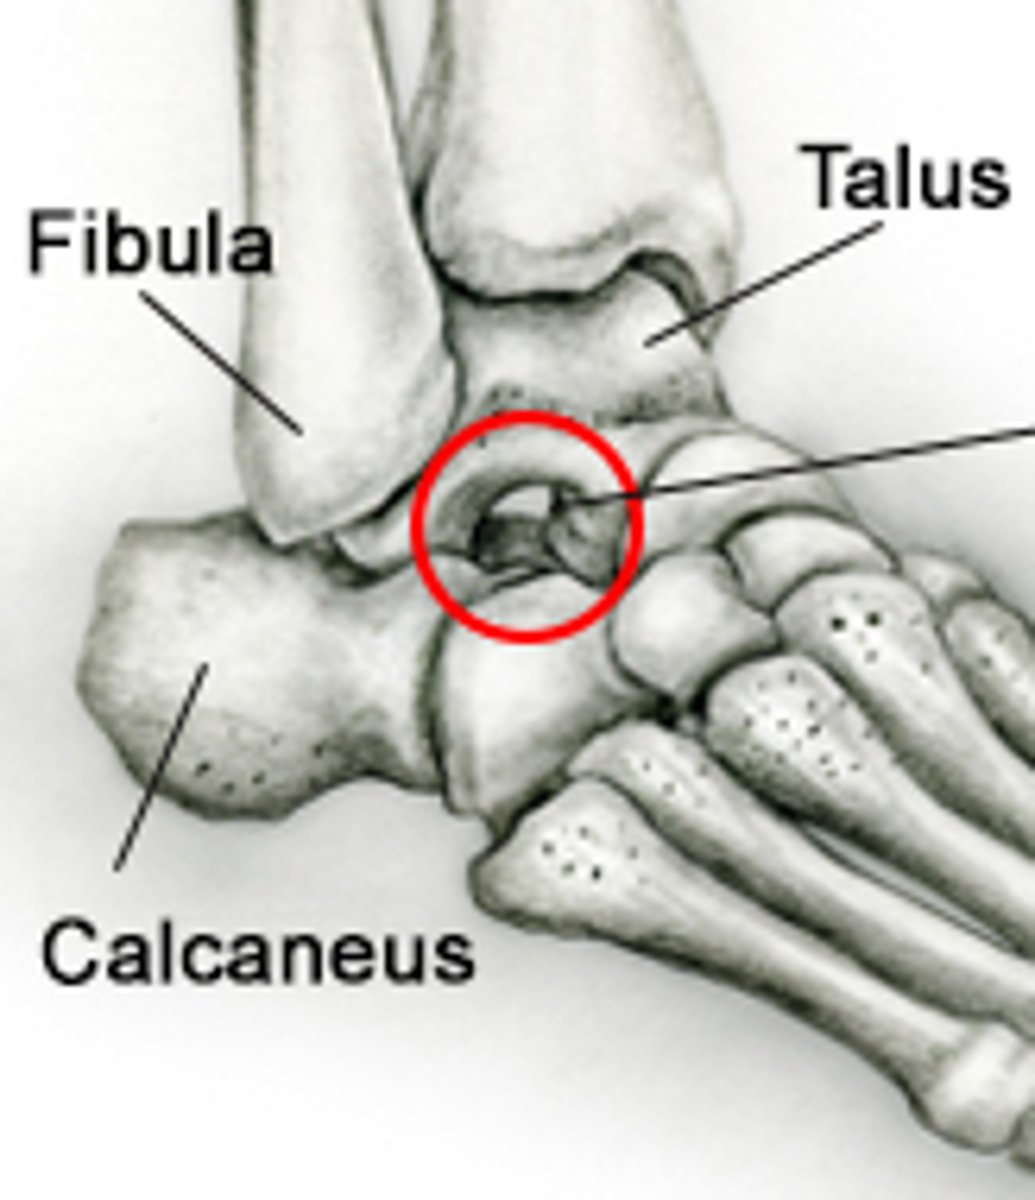

Talus

Superior trochlear surface

attachment surface for tibia

Lateral malleolar surface

Medial malleolar surface

Navicular articular surface (talonavicular joint)

Tarsal sinus (sinus between talus and calcaneus)

Calcaneus

Fibula

Lateral malleolus